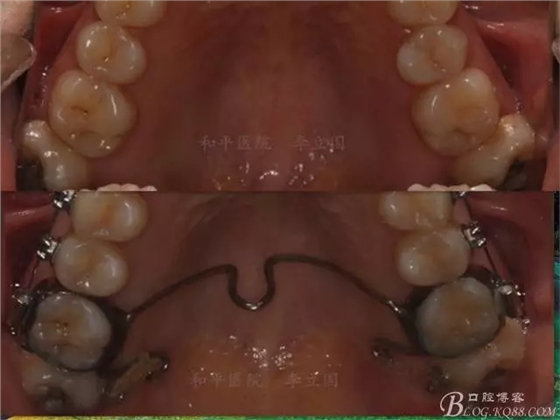

該病例主要為17、27頰側(cè)位同時(shí)伴有伸長(zhǎng),當(dāng)然種植支抗可以解決,但還有簡(jiǎn)單實(shí)用的辦法嗎?如圖,在橫腭桿遠(yuǎn)中延伸出牽引鉤,位置盡量遠(yuǎn)離合平面,7粘舌側(cè)扣,牽引力的方向?yàn)閴旱图吧嘞?,下圖為兩個(gè)月的效果,17已到位,27還未到位。